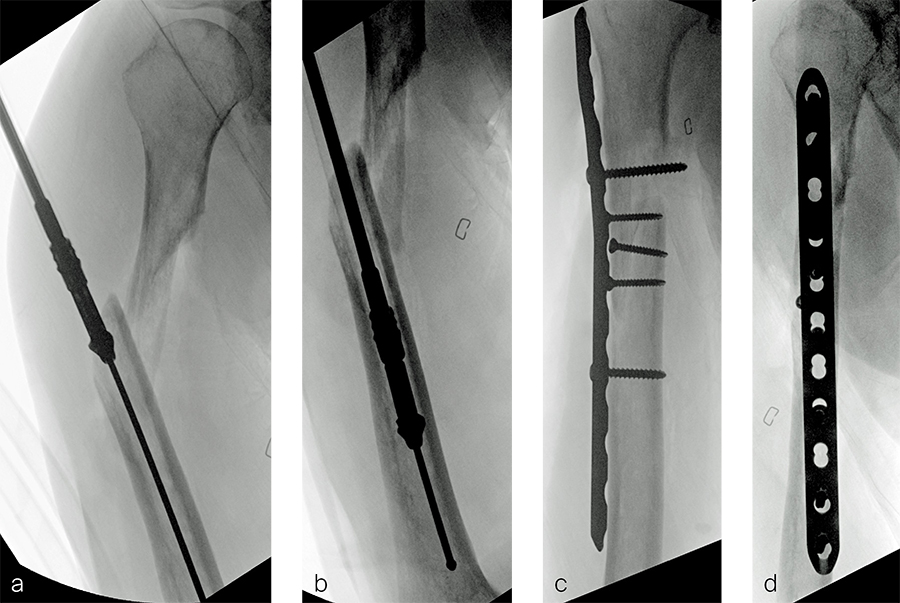

After debridement and resection of the pseudarthrosis, we accessed the distal segment of the humeral canal and used a small caliber RIA 2 reamer head to harvest intramedullary bone graft (Fig 8) for final plate fixation (Fig 9).